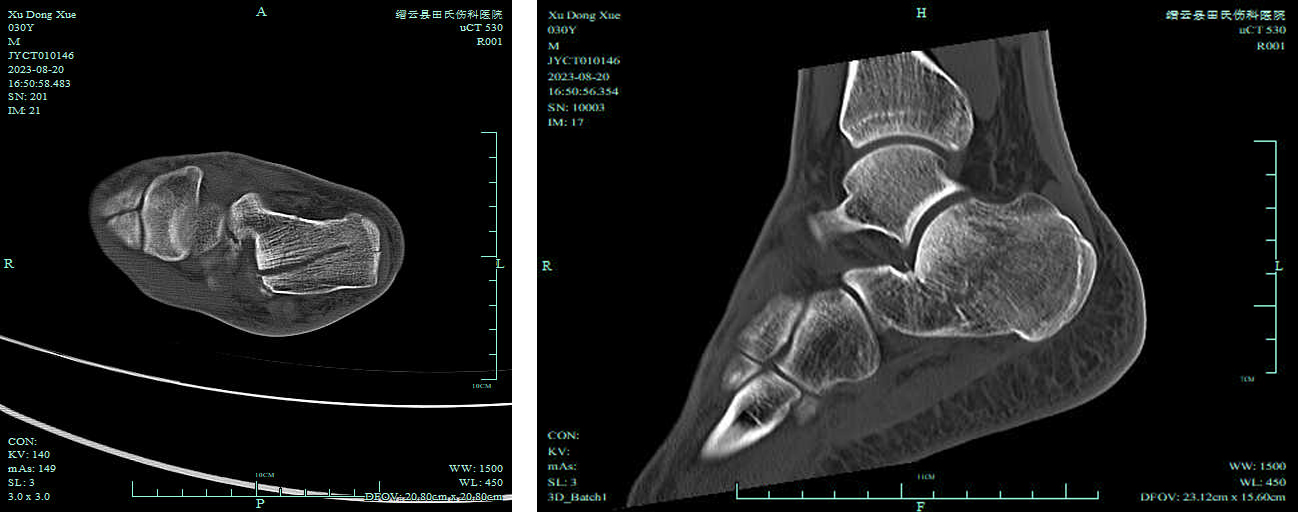

跟骨骨折分型

跟骨骨折可分为关节外骨折和关节内骨折。其中关节内骨折的CT分型有多种方法,最常用的是Sanders分型,其分型以冠状面及矢状面CT扫描为基础,分为4型。方法为选择后距下关节的最大面,用A、B两线由外向内将距骨面3等分,则跟骨被对应的A、B两线分为3部分,即内侧柱、中柱和外侧柱,C线对应距骨面内侧缘,A线对应外侧缘。

Ⅰ型:为所有无位移的关节内骨折,而不管有多少条骨折线。此型不许手术治疗。

Ⅱ型:出现位移的关节内骨折,并根据相应原发骨折线的位置分为A、B、C三个亚型。

Ⅲ型:后关节面出现2根骨折线,并根据其部位分AB、BC以及AC三个亚型,各亚型均有一中央凹陷骨折段。

Ⅳ型:包括那些严重的粉碎性骨折,后关节面出现4个骨折块。

SandersⅡ型、SandersⅢ型及SandersⅣ型常需采取外科手术复位治疗,对严重的凹陷性骨折区必要时还需做植骨术辅助治疗。